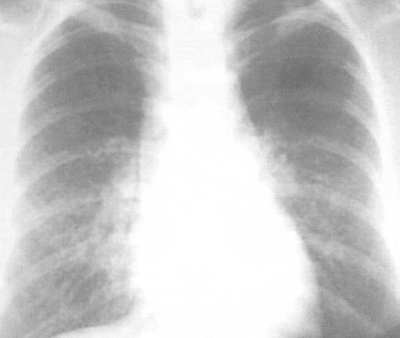

Рентген легких

Врач выслушает жалобы пациента и выполнит рентгеновские снимки легких. В сомнительных случаях врач направит пациента к пульмонологу.